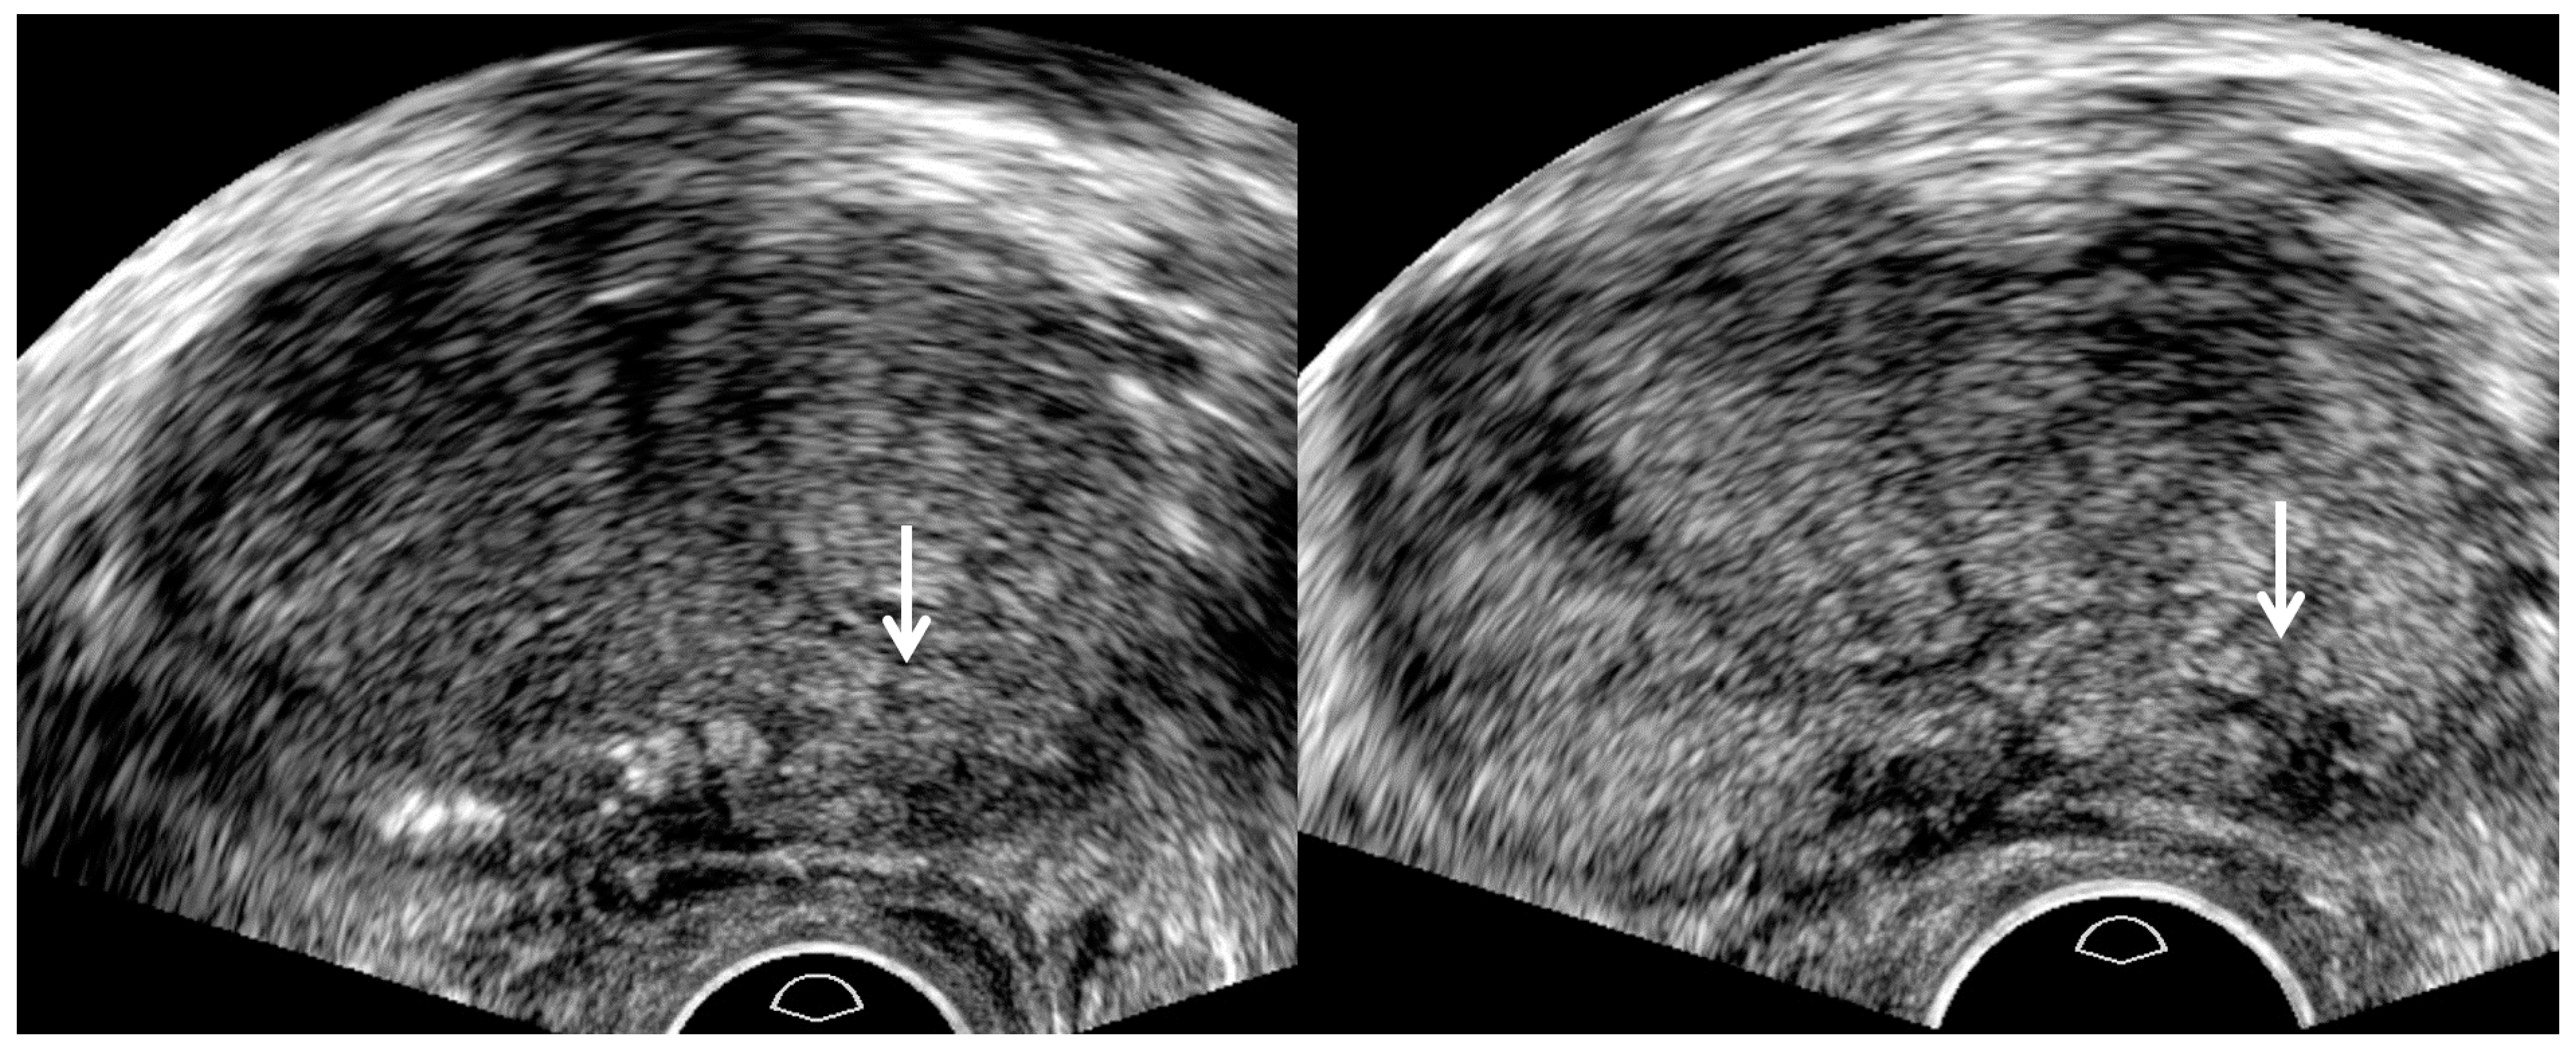

| US sequence | Harmonic imaging | Fundamental imaging |

| US artifacts | Rare | Frequent |

| Dynamic range | High | Low |

| Image resolution | High | Low |

| Tissue contrast | Low | High |